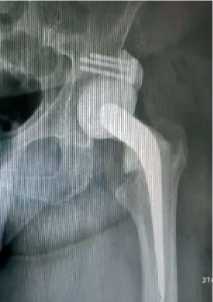

У 7 пациентов на фоне протекания септического коксита были отмечено формирование значительных анатомических изменений тазовой кости в области вертлужной впадины, в частности, – недостаточность верхнего края вертлужной впадины, что не позволяло устойчиво имплантировать головку цементного спейсера. В таких случаях на 1-м этапе хирургического лечения была осуществлена установка спейсера с созданием цементного надацетабулярного навеса по запантентованной методике (рисунок 3) [33].

Рисунок 3 . Спейсер с армированным навесом у пациента с кокситом и дефектом тела подвздошной кости